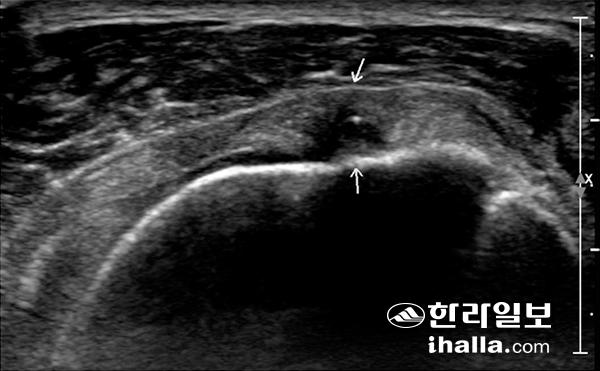

초음파 검사에서 회전근개 파열이 저에코의 결손으로 보이고 있다.

먼저 초음파 검사를 실시하면 우리 몸의 건(힘줄) 및 인대의 손상을 알아낼 수 있다. 우리 몸의 건(힘줄) 및 인대는 주로 외상에 의해 파열 등이 생길 수 있으며, 어깨 관절 주변의 건(힘줄)의 경우에는 외상과 함께 노화에 의해서도 파열이 생길 수 있다. 이 경우 초음파를 진단에 이용할 수 있다. 대부분은 어깨, 팔꿈치, 손가락 등 관절 주변의 건(힘줄) 및 인대 손상의 진단을 비교적 정확하게 내릴 수 있으며, 수술이 필요하거나 조금 더 자세한 검사가 필요할 때 MRI 등의 검사를 추천하게 된다. 물론 모든 건(힘줄) 및 인대의 파열을 진단할 수는 없어 뼈 사이에 깊숙이 위치한 무릎 인대 등은 MRI 검사가 진단에 더 많은 도움을 줄 수 있기도 하다. 이와 함께 주로 외상에 의해 발생하는 근육의 파열도 초음파 검사를 통해 진단할 수 있다.